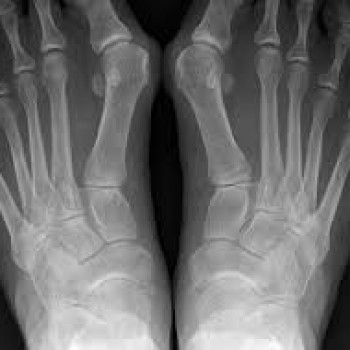

Вальгусная деформация большого пальца стопы - 600 грн

Болезненные ощущения в области большого пальца стопы вызванные отклонением большого пальца внутрь.

Это вызвано поперечным плоскостопием, в результате которого происходит распластание плюсневых костей, расширение передней части стопы и отклонение большого пальца внутрь – вальгусное отклонение.

Я с этим в корне не согласен, потому что мышцы приводящие большой палец к этому не имеют косвенного отношения. Вся причина в укороченной мышце длинного разгибателя большого пальца. Здесь мышцы приводящие большой палец пере растягиваются. Обратите внимание как уходит наружу плюсневая кость. Прикладная кинезиология доказывает, что это так. Мы это делаем на практике, находим причину укорочения мышцы или мышц на обеих ногах. На первой и второй стадии развития заболевания можно успешно устранить эту проблему. При третьей стадии уже необходимо будет дополнительно прибегнуть к дополнительным процедурам способным убрать воспалительный процесс.